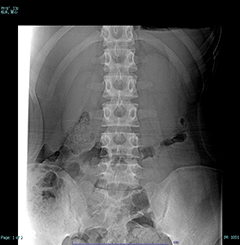

骨の病変を見るCT like images

腰椎椎間板ヘルニア